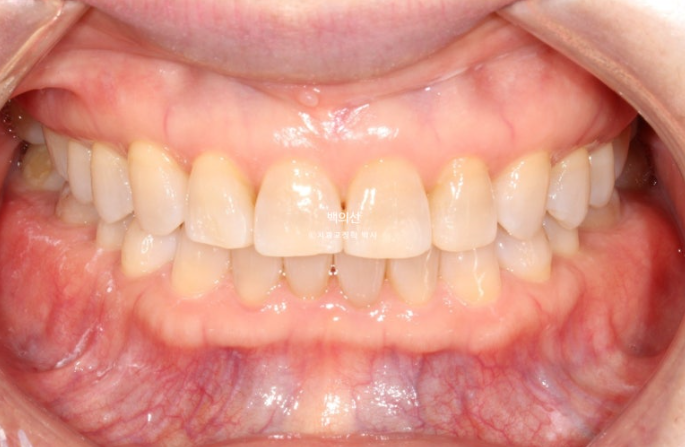

25.08

25년 5월부터 7월까지 7개 추가장치를 모두 낀 후 치료를 마쳤습니다.

원래 좋았던 어금니 교합은 잘 유지가 되었씁니다.

이제 전 후 비교 보겠습니다.

25.02~25.08

인비절라인 익스프레스로 과개교합 개선이 가능합니다.

앞니 교합이 얕아지면서 윗니에 가려 잘 안 보이던 아래 앞니가 이제 절반 이상 보이게 되었습니다.

레진으로 메꿔놓았던 틈은 교정으로 완벽하게 사라졌습니다.

앞니 뿐 아니라 송곳니가 튀어나왔던 부분도 배열이 개선이 되었습니다.